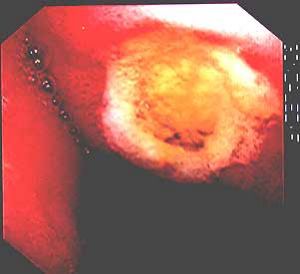

慢性潰瘍性結腸炎 病理病變開始時為黏膜基底Lieberkülin隱窩有圓細胞和中性多核細胞浸潤,形成隱窩膿腫,光鏡下可見覆蓋的上皮細胞染色過淺和空泡形成。電鏡中可見線粒體腫脹,細胞間隙增寬以及內漿網質增寬。隨著病變進展,隱窩膿腫聯合和覆蓋上皮脫落,形成潰瘍。潰瘍鄰近則有相對正常的黏膜,但有水腫,成為自肉樣外貌,在相鄰的潰瘍間變得很孤立。潰瘍區被膠原和肉芽組織放縱地生長所占領,並深入潰瘍,但罕有穿透肌層者。在暴髮型慢性潰瘍性結腸炎和中毒性巨結腸時,這些病變可穿透整個腸壁,導致穿孔。所幸,這種類型的病變不多見,分別占15%和3%。病理變化為臨床表現提供了清楚的解釋。幾乎每天有20次以上的血便。因為腸壁光剝、明顯變形的黏膜已不能吸收水和鈉,每一次腸蠕動都將從暴露的肉芽組織面上擠出大量血液。早期X線表現為結腸袋消失是黏膜肌層麻痹之故,鋇灌腸中結腸短縮和僵直呈煙囪管狀則是反覆損傷後瘢痕形成的結果。

診斷上主要依靠纖維結腸鏡檢,因為約在90%~95%患者直腸和乙狀結腸受累,因此事實上通過纖維乙狀結腸鏡檢已能明確診斷。鏡檢中可看到充血、水腫的黏膜,脆而易出血。在進展性病例中可看到潰瘍,周圍有隆起的肉芽組織和水腫的黏膜,貌似息肉樣,或可稱為假息肉形成。在慢性進展性病例中直腸和乙狀結腸腔可明顯縮小,為明確病變範圍,還是套用纖維結腸鏡作全結腸檢查,同時作多處活組織檢查以便與克隆結腸炎鑑別。

慢性潰瘍性結腸炎 腸鏡表現2、黏膜活檢組織學檢查呈炎症性反應,同時可見糜爛、潰瘍、隱窩膿腫、腺體排列異常、杯狀細胞減少及上皮變化。